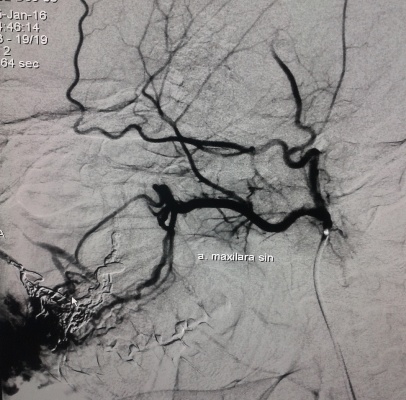

În secţia Chirurgie endovasculară s-a adresat pacientul S., bărbat de 30 ani, cu o formaţiune tumorală a feţei, cu senzaţie de pulsaţie permanentă, cu dureri periodice şi sîngerări frecvente la periaj dentar. Formaţiunea s-a dezvoltat treptat, iar în perioada pubertară a înregistrat o creştere accelerată. O serie de investigaţii (Angio-RMN şi Duplexul arterial) a stabilit diagnosticul de Malformaţie arteriovenoasă, care este o anomalie vasculară activă hemodinamic, cu flux sanguin rapid, cu afluenţi arteriali şi vene dilatate.

S-a utilizat procedura minim-invazivă endovasculară, care constă în cateterizarea supraselectivă a aferentelor arteriale a malformaţiei, cu embolizarea ulterioară a acestora pîna la stoparea fluxului de sînge prin malformaţie. De obicei, o astfel de procedură durează de la 40 minute pînă la două ore. Extrem de rar pot apărea complicaţii de ordin local (hematom, tromboză, fistulă) sau la nivelul regiunii malformaţiei (ulceraţie a mucoasei cu hemoragie, embolizarea ţesutului nedorit cu necroze). Scopul intervenţiei a fost de a micşora volumul malformaţiei (cu lichidarea ei în varianta ideală), dar şi de a atribui un aspect estetic. Astfel de proceduri pot fi asociate cu metode chirurgicale reconstructive de excizie a malformaţiei sau sclerozare, în cazuri selecte, care pot produce deformaţiuni şi cicatrici nedorite.